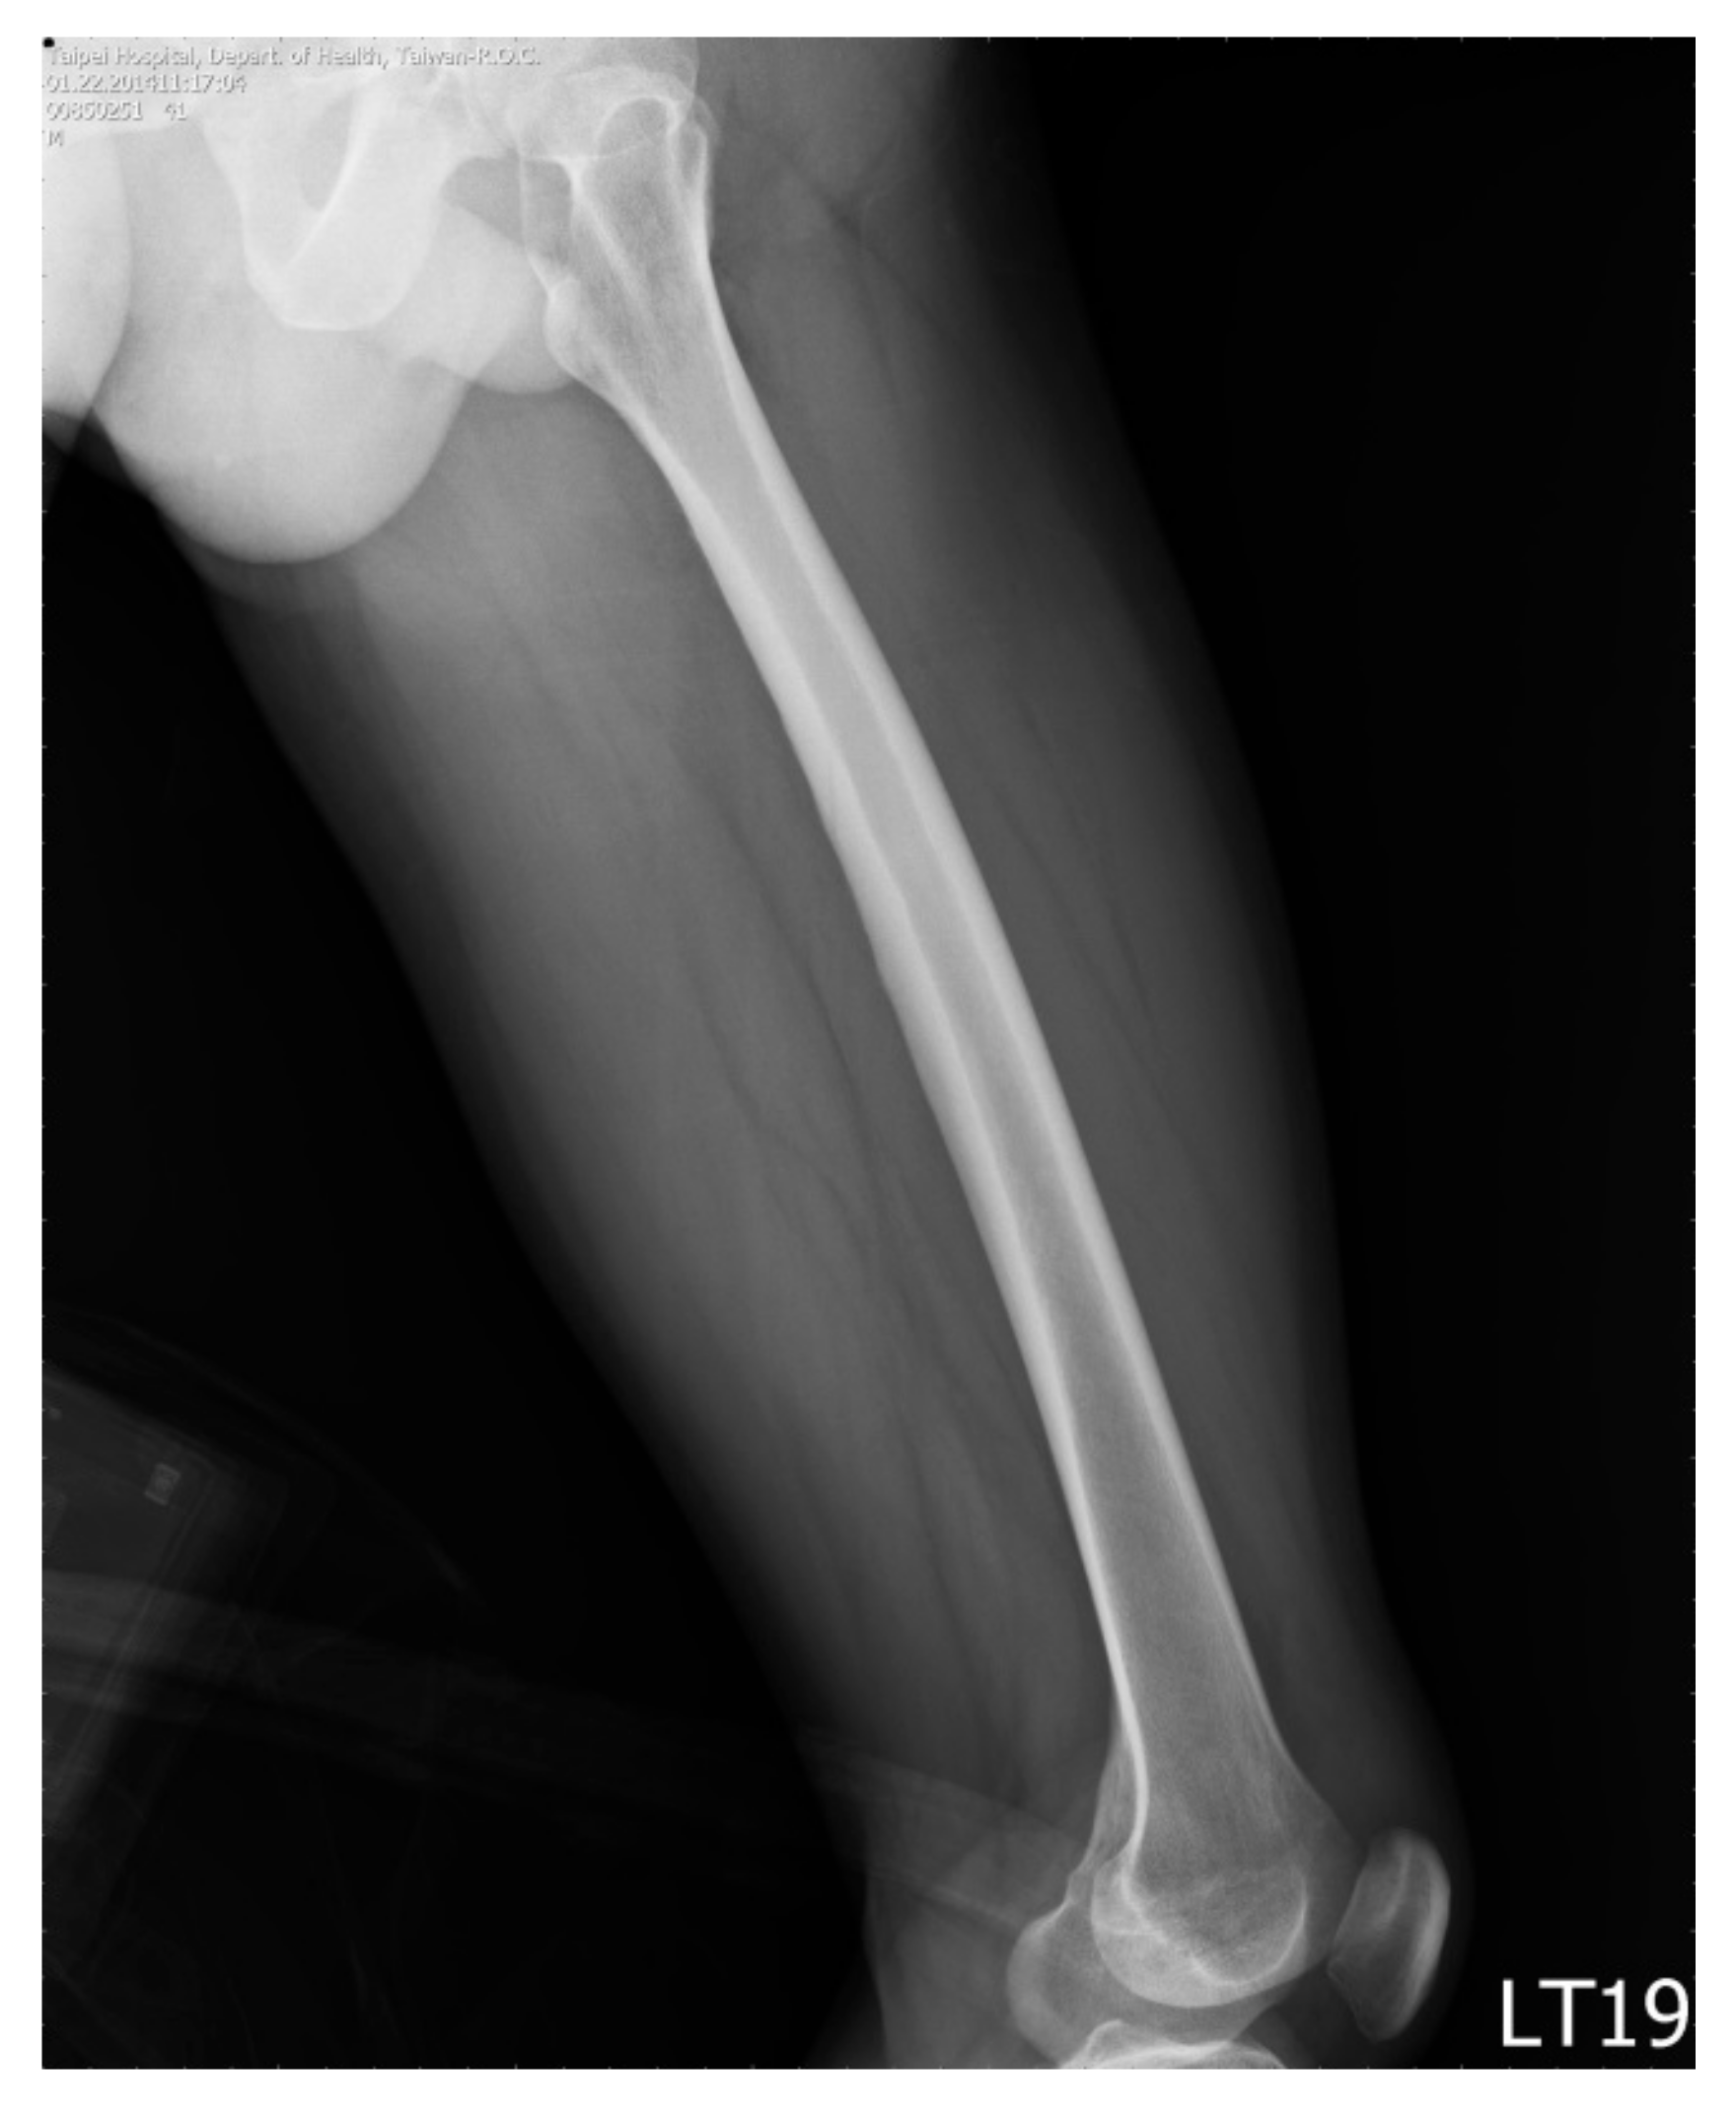

Once we had determined the proximal and distal ends, we started to draw the upper and lower borders on the image from the proximal end to the distal end, respectively. For each image, we drew the outlines of the femur and the borders of the medullary canal to calculate the curvature of the femur (cortical bow) (Figure 4a) and that of the interior medullary canal (medullary bow) (Figure 4b).

Figure 4. The marked (drawn) outline of cortical border (a) and the marked (drawn) outline of medullary canal (b).